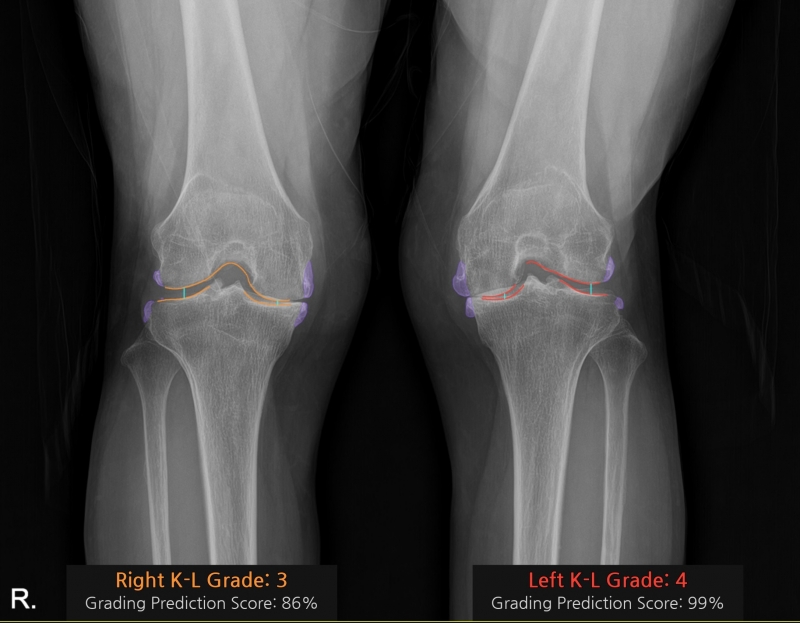

코네보 코아는 무릎 X-ray 영상을 분석해 관절염 심각도를 ‘K-L(Kellgren–Lawrence) 등급’으로 판정하고, 골극과 관절 간격을 시각화해 제공한다.

이를 통해 진단의 일관성을 높이고 환자와 상담 시 유용한 시각자료로 활용할 수 있다.

공동 연구자인 김성환 정형외과 교수는 “AI 솔루션이 관절염 상태를 직관적으로 보여줘 환자 이해도가 크게 향상됐다”며 “실제 사용 경험에서도 만족도가 매우 높다”고 말했다.